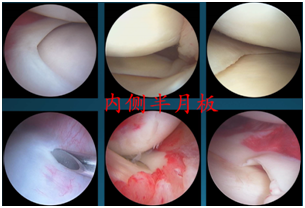

损伤的半月板